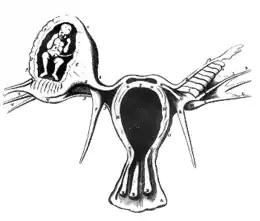

La grossesse extra-utérine (GEU), ou grossesse ectopique, est une grossesse se développant hors de l'utérus. La très grande majorité des grossesses extra-utérines sont des grossesses dans la trompe de Fallope ou grossesses tubaires. La grossesse extra-utérine justifie une urgence chirurgicale dans sa forme rompue. Son diagnostic est de plus en plus précoce permettant d'éviter sa rupture et la mise en jeu du pronostic vital et permettant un traitement non chirurgical sous certaines conditions strictes.

Neuf dixièmes des grossesses extra-utérines ont lieu au niveau d'une trompe de Fallope[2], reliant l'ovaire à l'utérus. On parle alors de grossesse tubaire. Les rares cas de grossesses extra-tubaires sont de diagnostic plus difficile, entraînant un taux de complications plus important.

Les formes non tubaires sont rares. La localisation ampullaire est la plus fréquente. Elle est parfois de révélation tardive, pouvant réaliser un avortement tubo-abdominal.

La localisation peut être ovarienne, isthmique (de révélation précoce), interstitielle (avec rupture au niveau de la corne utérine), abdominale (avec implantation sur n’importe quel organe) ou rétro-utérin.